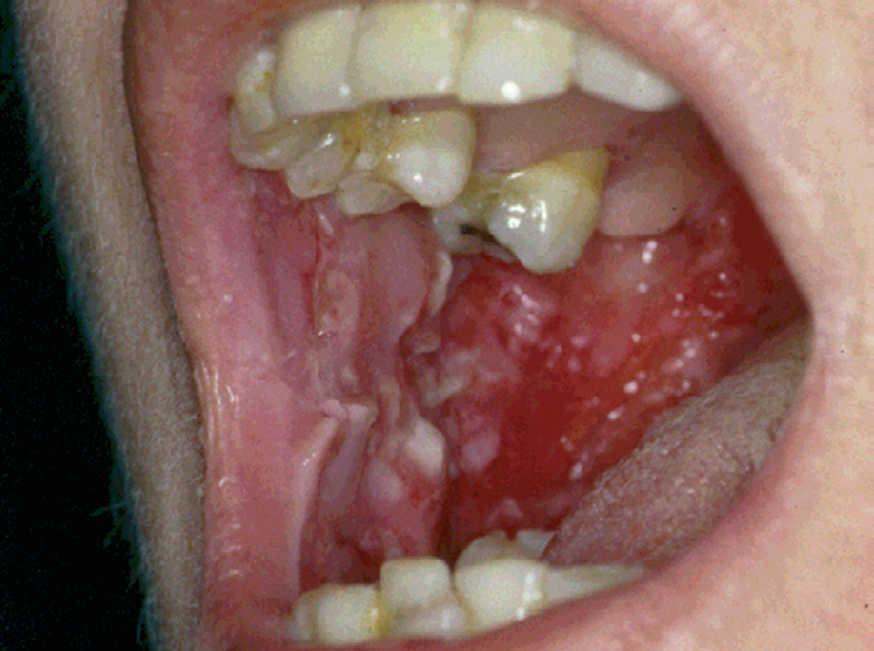

La forma de comienzo del cuadro ocurre en un porcentaje elevado de los casos, alrededor del 50-70 % de los mismos, con lesiones mucosas. La afectación mucosa es muy característica y frecuente, siendo un hecho casi constante que aparece en la evolución del PV. De ellas, la mucosa oral es la más frecuentemente interesada y, como ya hemos referido, en ocasiones marca el comienzo de la enfermedad. Estas lesiones suelen ser dolorosas y son resistentes al tratamiento. En la mucosa yugal las lesiones son muy evocadoras en forma de erosiones irregulares, grandes y extensas, que dejan al descubierto una mucosa hiperémica, o a veces cubiertas de lesiones blanquecinas (fig. 6). En los labios pueden existir erosiones y costras con un collarete descamativo o con restos epidérmicos (fig. 7). Cuando afecta a la mucosa gingival va a dar origen a erosiones alrededor de la implantación dentaria. No infrecuentemente se afecta el paladar tanto duro como blando en forma de erosiones aisladas o coalescentes, así como la lengua, en donde las lesiones erosivas pueden ser dolorosas (fig. 8). Otras mucosas, como la conjuntiva, la mucosa de la nariz u otras, pueden estar afectadas, ocurriendo en ocasiones la afectación de dos o más mucosas simultáneamente. En los casos en los que la enfermedad tiende a ser más grave se pueden encontrar lesiones en la faringe, laringe, esófago, mucosa anal y genital acompañados de dolor 119.

Fig. 6.--Erosiones en mucosa yugal en pénfigo vulgar.